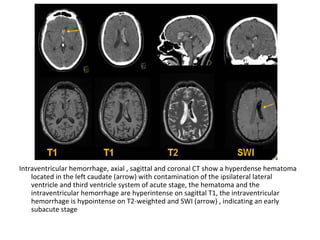

9-Hemorrhage :

-Hemorrhagic transformation is a little variably

used and collectively refers to two different

processes which have different incidence ,

appearance and prognostic implications ,

these are :

a) Petechial hemorrhage

b) Intracerebral hematoma

b) In the case of secondary hematomas :

-The radiographic features on both CT and MRI are

merely a summation of the features of a ischemic

infarct with superimposed cerebral hemorrhage

-The amount of hemorrhage relative the size of the

infarct can vary widely but usually it is possible to

identify significant areas of the brain which are

infarcted but not hemorrhagic

-This may not be the case if the hemorrhage is large

and the underlying infarct small

-By the time secondary hematomas form , the

underlying infarct should be easily seen

and will appear as a region of low attenuation

involving both the white matter and the

overlying cortex

-Hemorrhage is often patchy , scattered

throughout the infarcted tissue and usually

represents only a small component of the

abnormal tissue

T1 , Hemorrhagic transformation is detected as areas of increased

signal intensity , the gyral pattern of increased signal intensity may

also represent cortical laminar necrosis

signal intensity